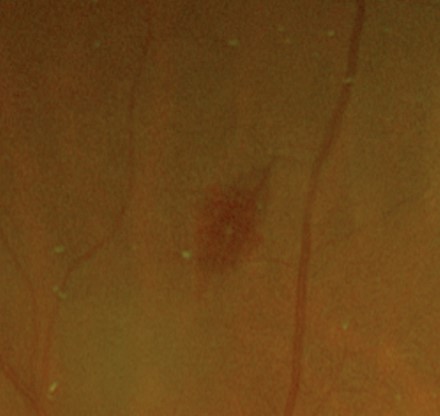

A Roth spot is a flame haemorrhage with a characteristic white centre. These haemorrhages are associated with a variety of systemic disease, most notably with bacterial endocarditis. Other associated conditions include leukemia, anaemia, hypertensive retinopathy, pre-eclampsia, diabetic retinopathy, human immunodificiency virus (HIV), pre-eclampsia, shaken baby syndrome and anoxia.

Roth spots are the result of retinal capillary rupture and intraretinal hemorrhage. The white centre of the lesion is composed of fibrin that has formed a fibrin-platelet "plug" at the site of capillary rupture.